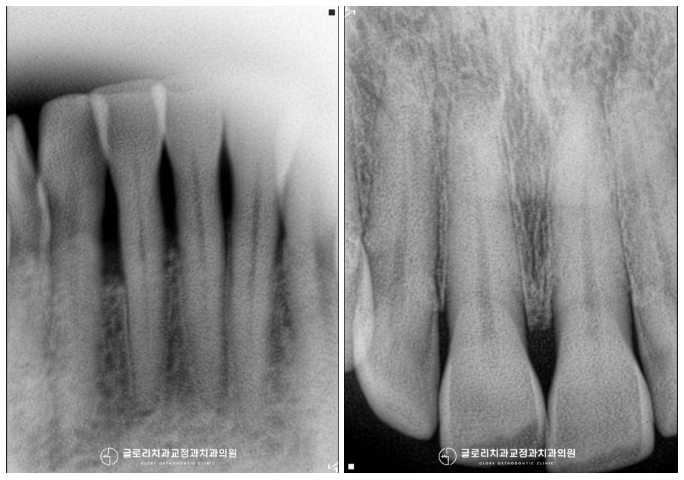

방사선 촬영으로 정밀검진을 시행하여

치근흡수나 치주 질환 등

다른 문제들이 없는지 꼼꼼하게 확인하는데요.

다행히 치열 개선을 진행해도

문제가 없을 거라는 판단이 들어

본격적으로 계획을 세우기로 했습니다.